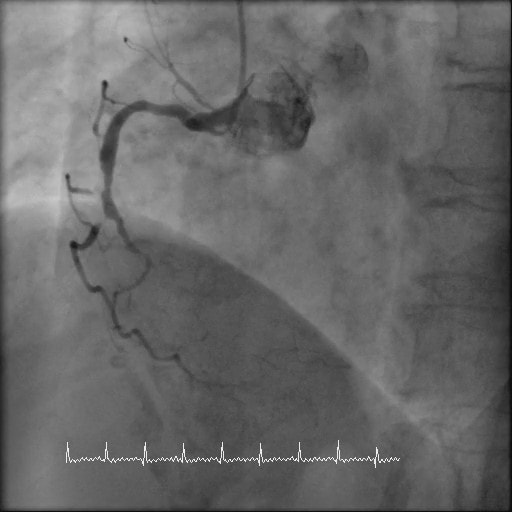

冠動脈バイパス術後の評価CT

CTでは、心臓に酸素や栄養を送る冠動脈と呼ばれる血管の状態(狭窄や閉塞)や、心臓の全体像を知ることができます。また、バイパスなど手術後の経過なども調べることができます。